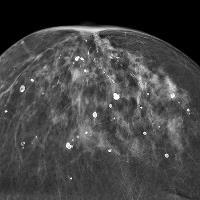

بیوپسی پستان نمونه‌ای از بافت مشکوک پستان را در اختیار پزشک قرار می‌دهد تا بتوان با استفاده از بررسی آن، هر گونه ناهنجاری در سلول‌هایی که تشکیل دهنده توده‌های پستانی هستند را شناسایی کرد. این آزمایش به دنبال، تصویر برداری از بافت پستان به روش‌های ماموگرافی و سونوگرافی و در صورت مشاهده توده‌های مشکوک انجام می‌شود و به پزشک در انتخاب بهترین روش درمان با این توده‌ها کمک می‌کند.

• نتایج ماموگرافی سینه نشان دهنده ناحیه‌ای مشکوک در بافت پستان باشد.

بیوپسی استریوتاکتیک

این نوع بیوپسی با استفاده از ماموگرافی برای تشخیص و علامت زدن محل دقیق قرارگیری توده مشکوک پستانی انجام می‌شود. برای این روش، بیمار به روی شکم خود روی تخت مخصوص بیوپسی دراز می‌کشد و سینه‌های خود را در حفره مخصوص تخت قرار می‌دهد. سپس سینه‌ها بین دو صفحه مخصوص دستگاه ماموگرافی قرار داده می‌شوند و رادیولوژیست یا پزشک با استفاده از یک شکاف نازک روی سطح سینه و وارد کردن سوزن یا لوله ساکشن مخصوص اقدام به نمونه برداری از بافت مشکوک پستان می‌کند.  گاهی نیز این روش به صورت نشسته انجام می‌شود. در طول انجام این فرایند بیمار باید حدود سی دقیقه بی حرکت باقی بماند.